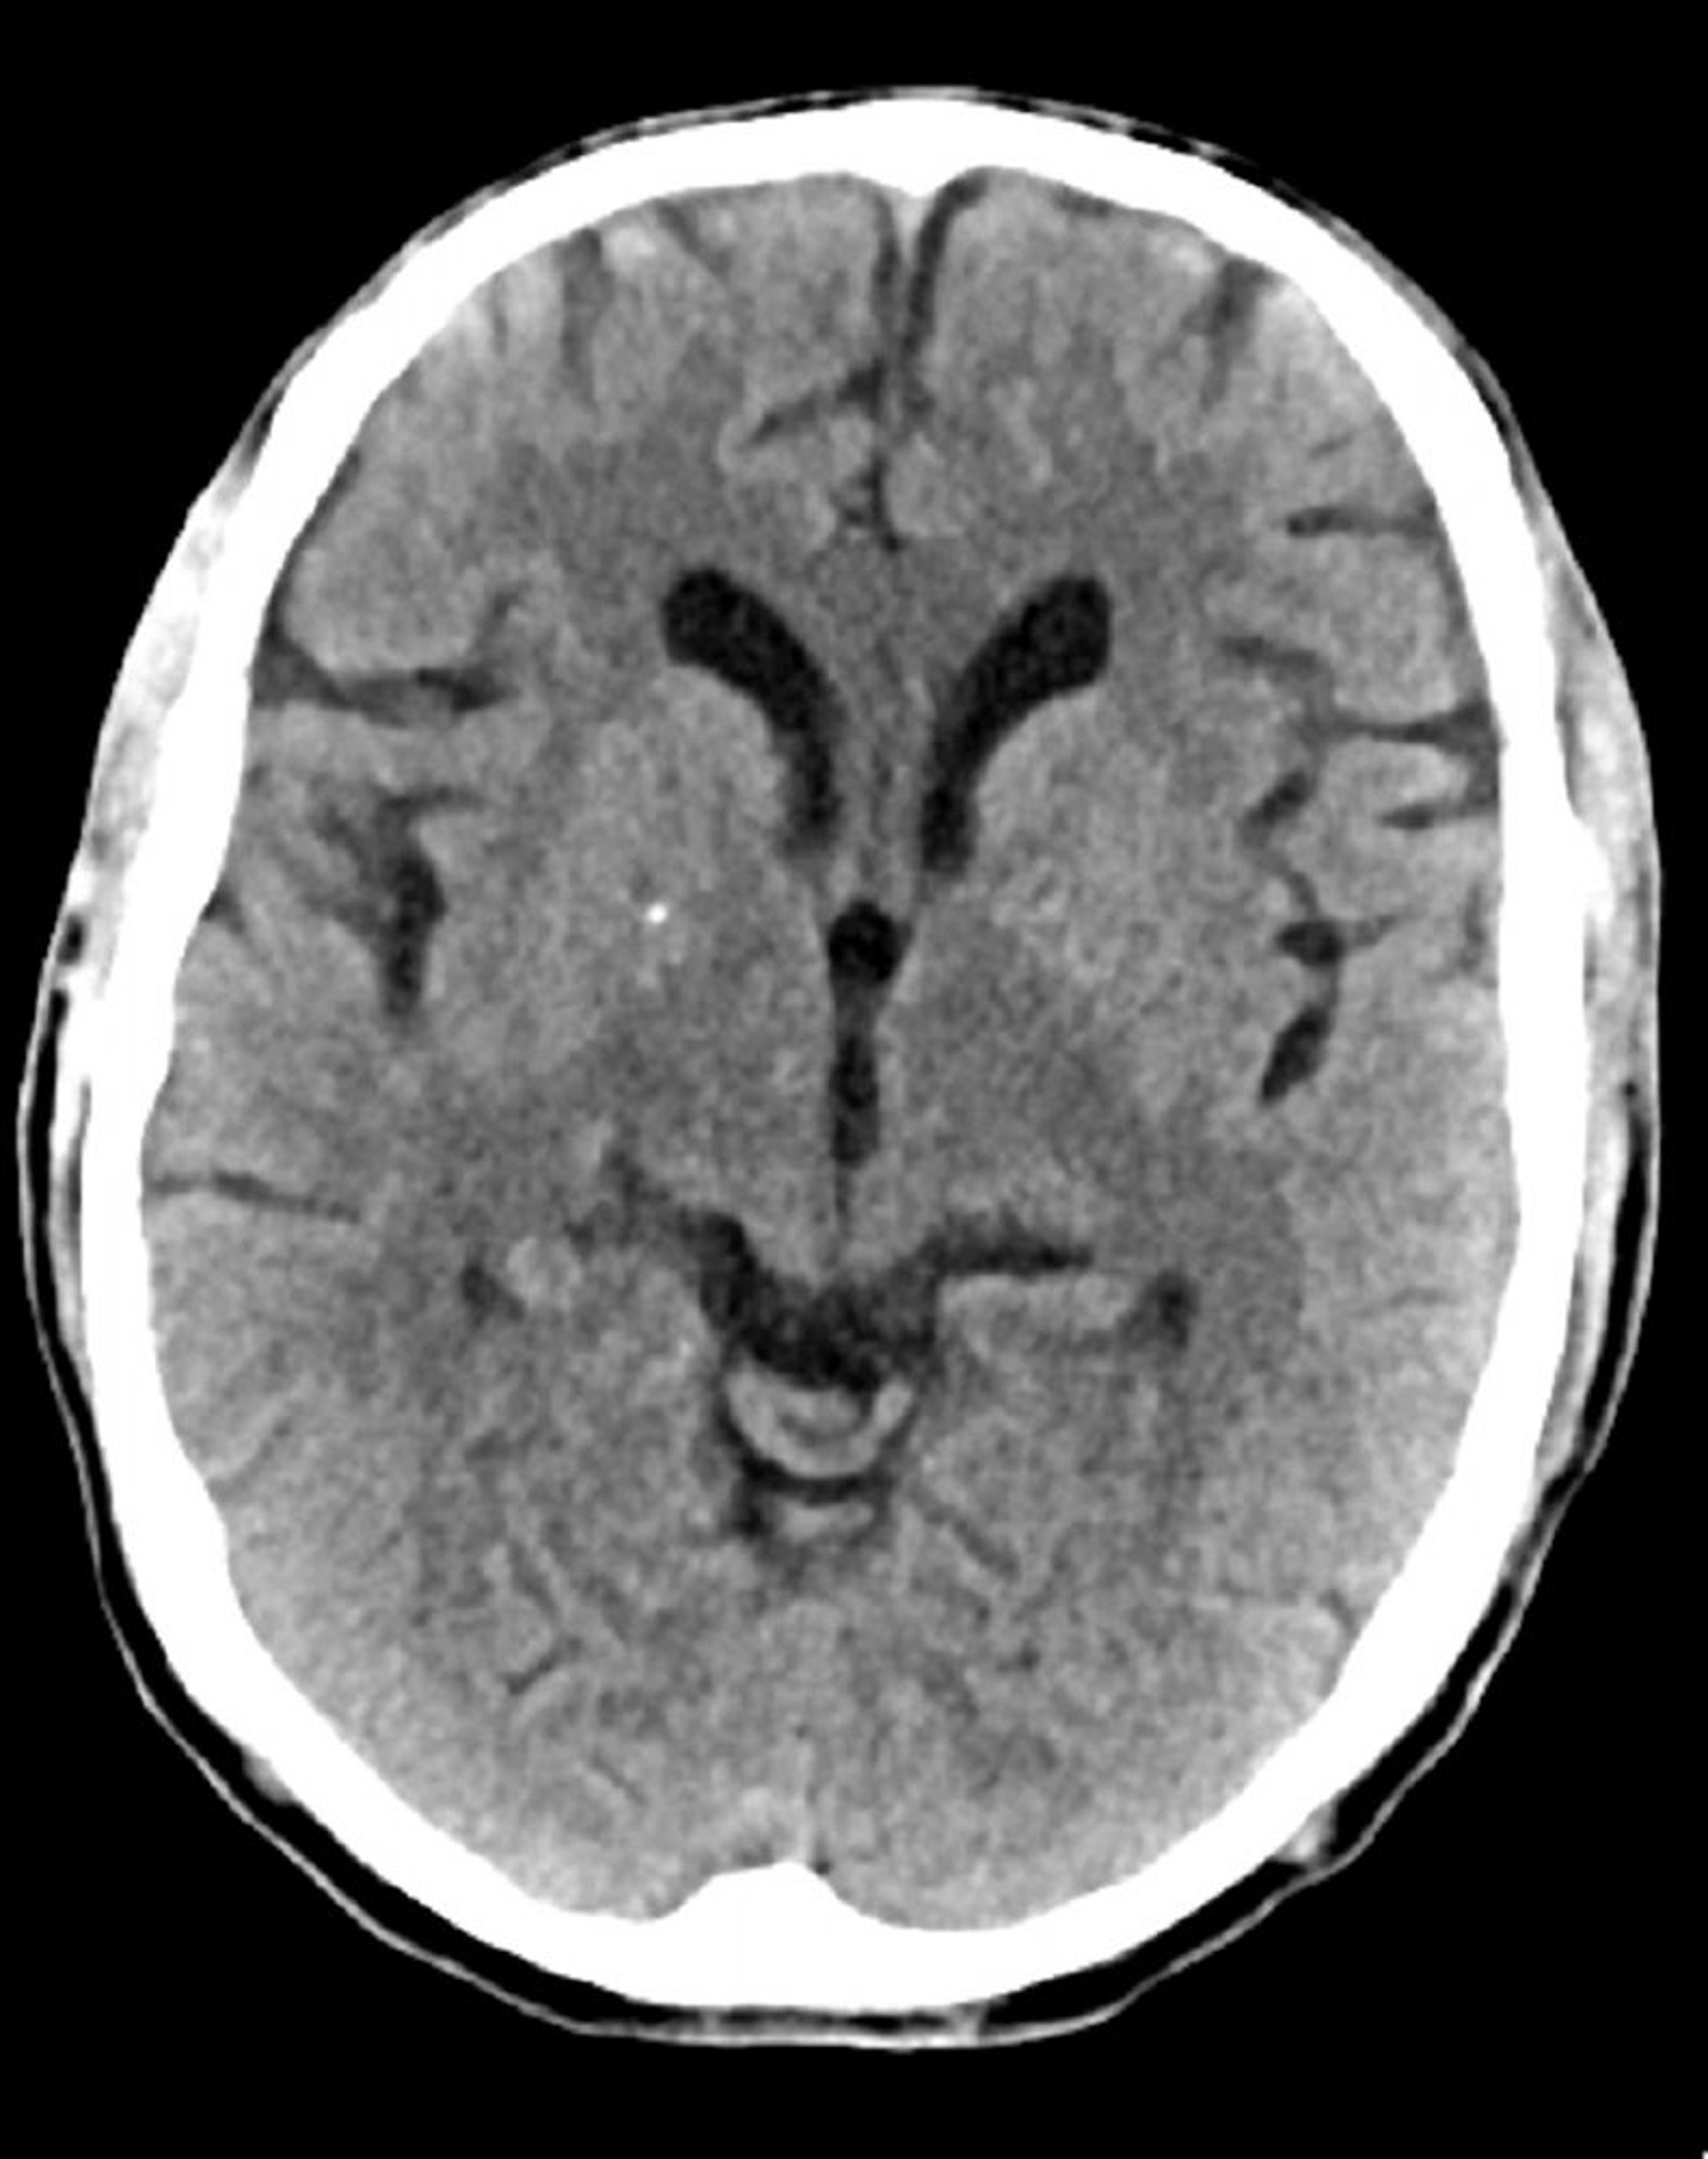

Tomografía computarizada craneal normal (adulto, 74 años)–diapositiva 6

Esta imagen es una tomografía computarizada craneal normal correspondiente a un adulto de 74 años. Cuando se compara con la tomografía computarizada craneal normal del adulto de 30 años de edad, se observa que los ventrículos y los sulcos son más grandes. Estos son hallazgos normales en este grupo de edad.